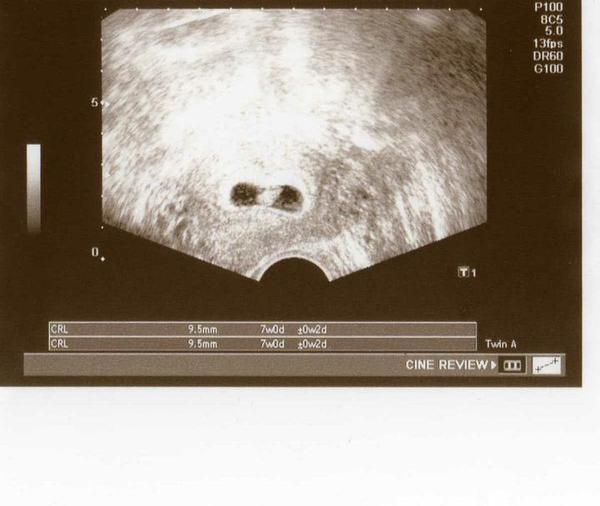

@evi789 ja ked som zostala tehu s malou to bolo okolo 8.februara a bola som vtedy chora a mala lieky a tie lieky som nemohla ani citit to bolo 18.februara a urobila test a boli dve ciarky ale u doktora som bola 29.februara som bola 4.tt pridavam foto a potom 7.tt